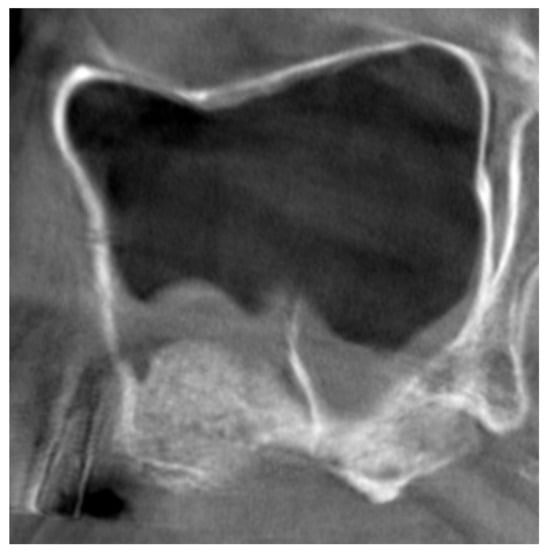

3.1. Clinical Report

3.2. CBCTs Assessments